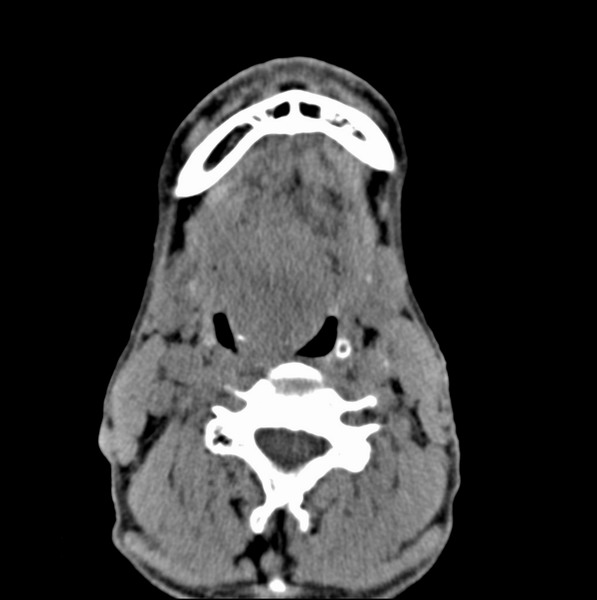

标题: CT19620:舌根肿物

男、60、舌根肿物。

舌垂直肌和横肌影处肿块影,边缘不规则,咽腭扁桃体及舌下间隙脂肪影消失,病变侵及口咽。

考虑-----舌根癌

舌跟软组织肿块,较大有坏死,钙化。结合年龄一般是恶性肿瘤。

舌根部较大软组织肿块,其内见坏死低密度区及钙化影;考虑舌根癌可能。

支持考虑舌根癌或会厌癌